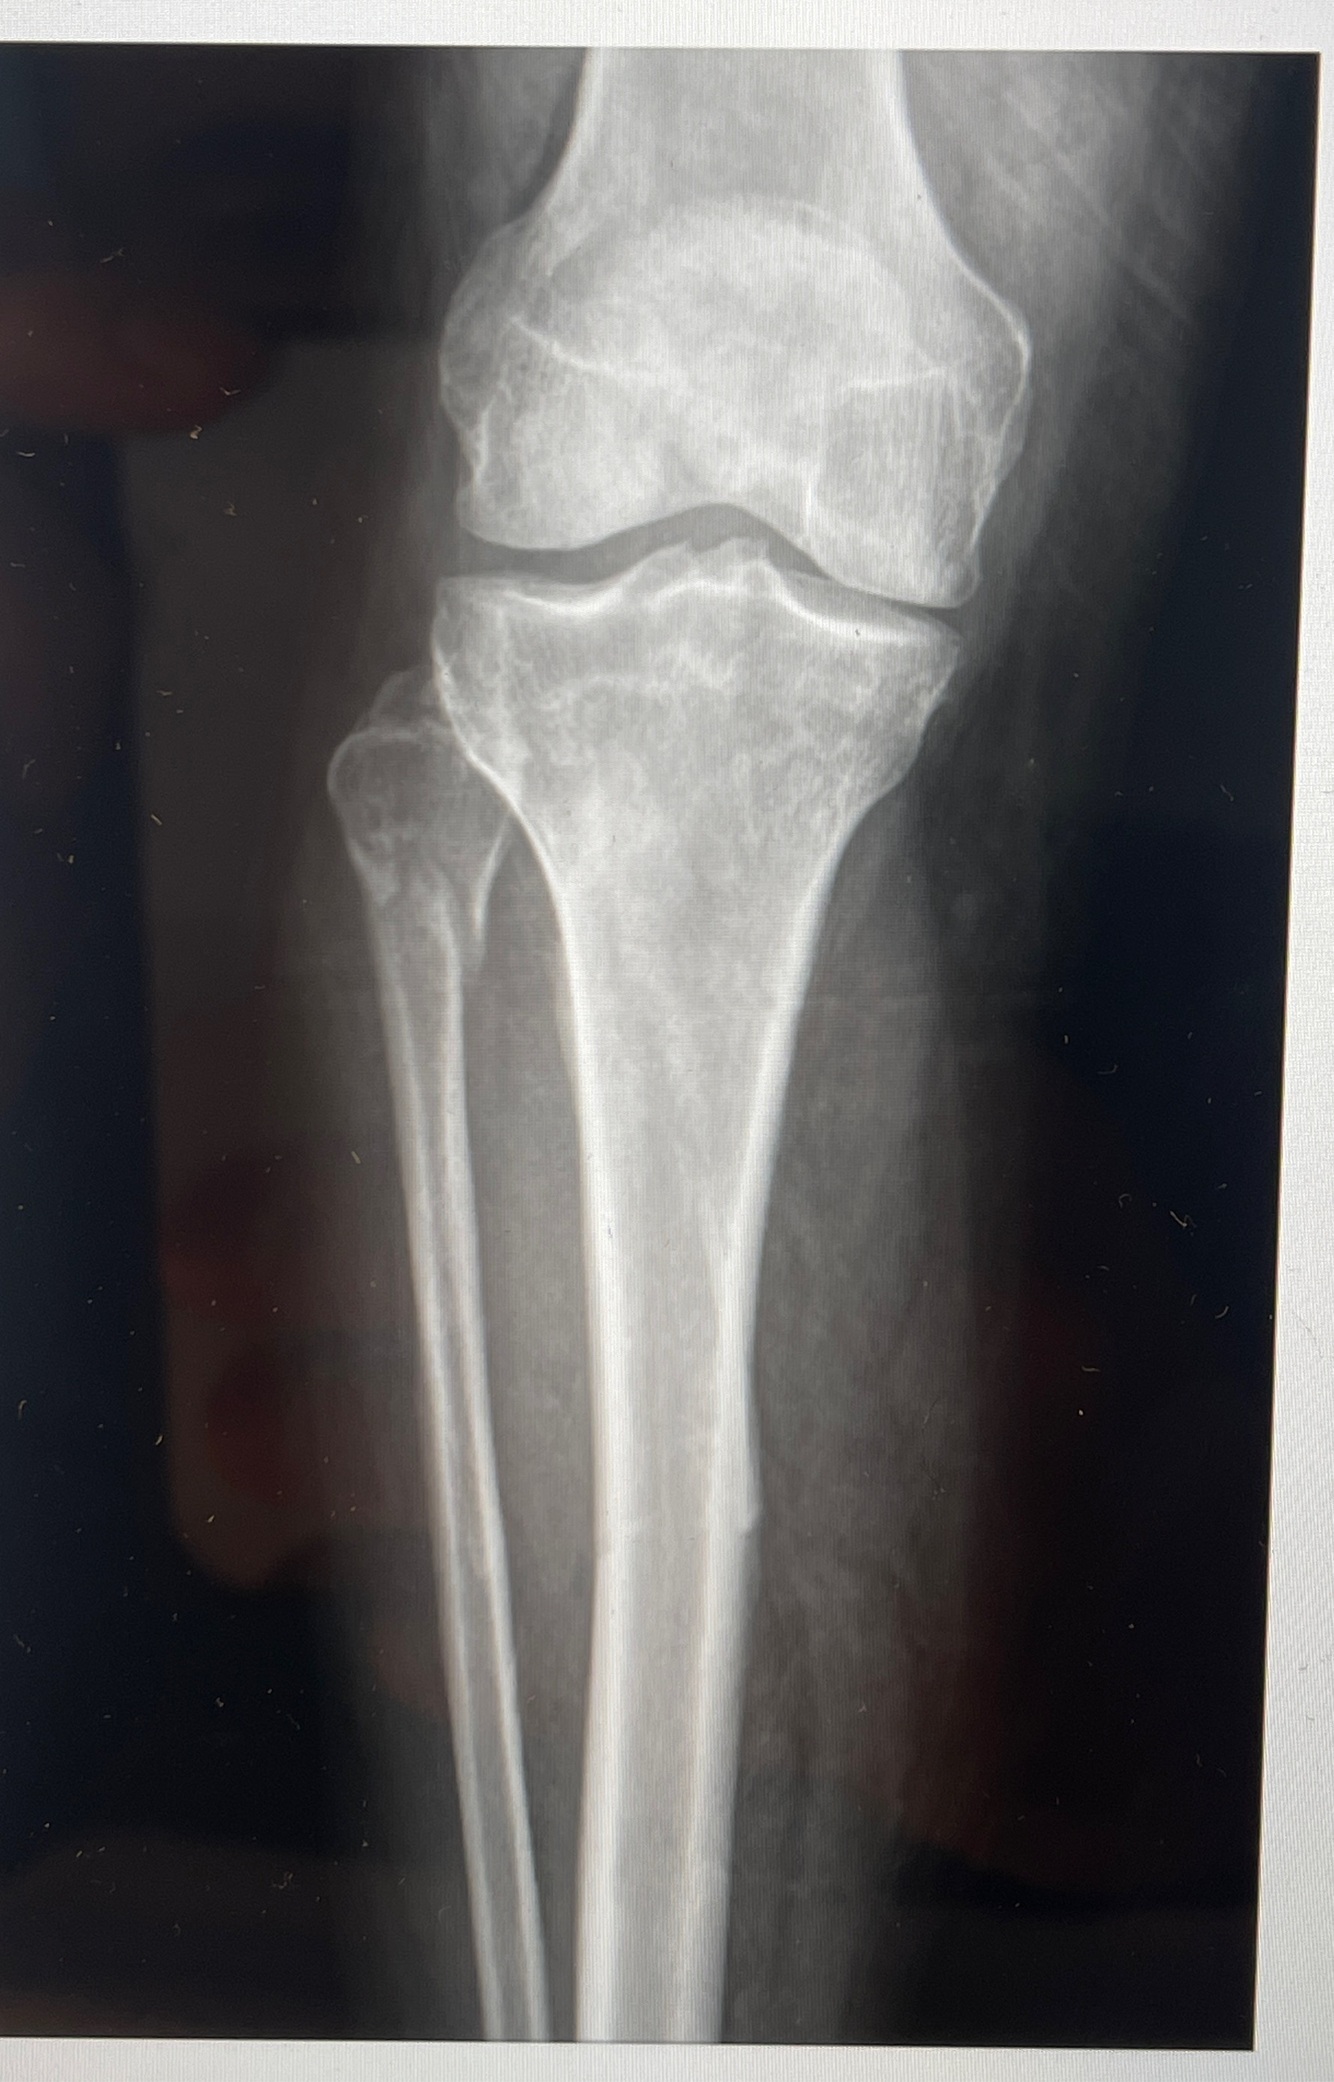

20

Q

A